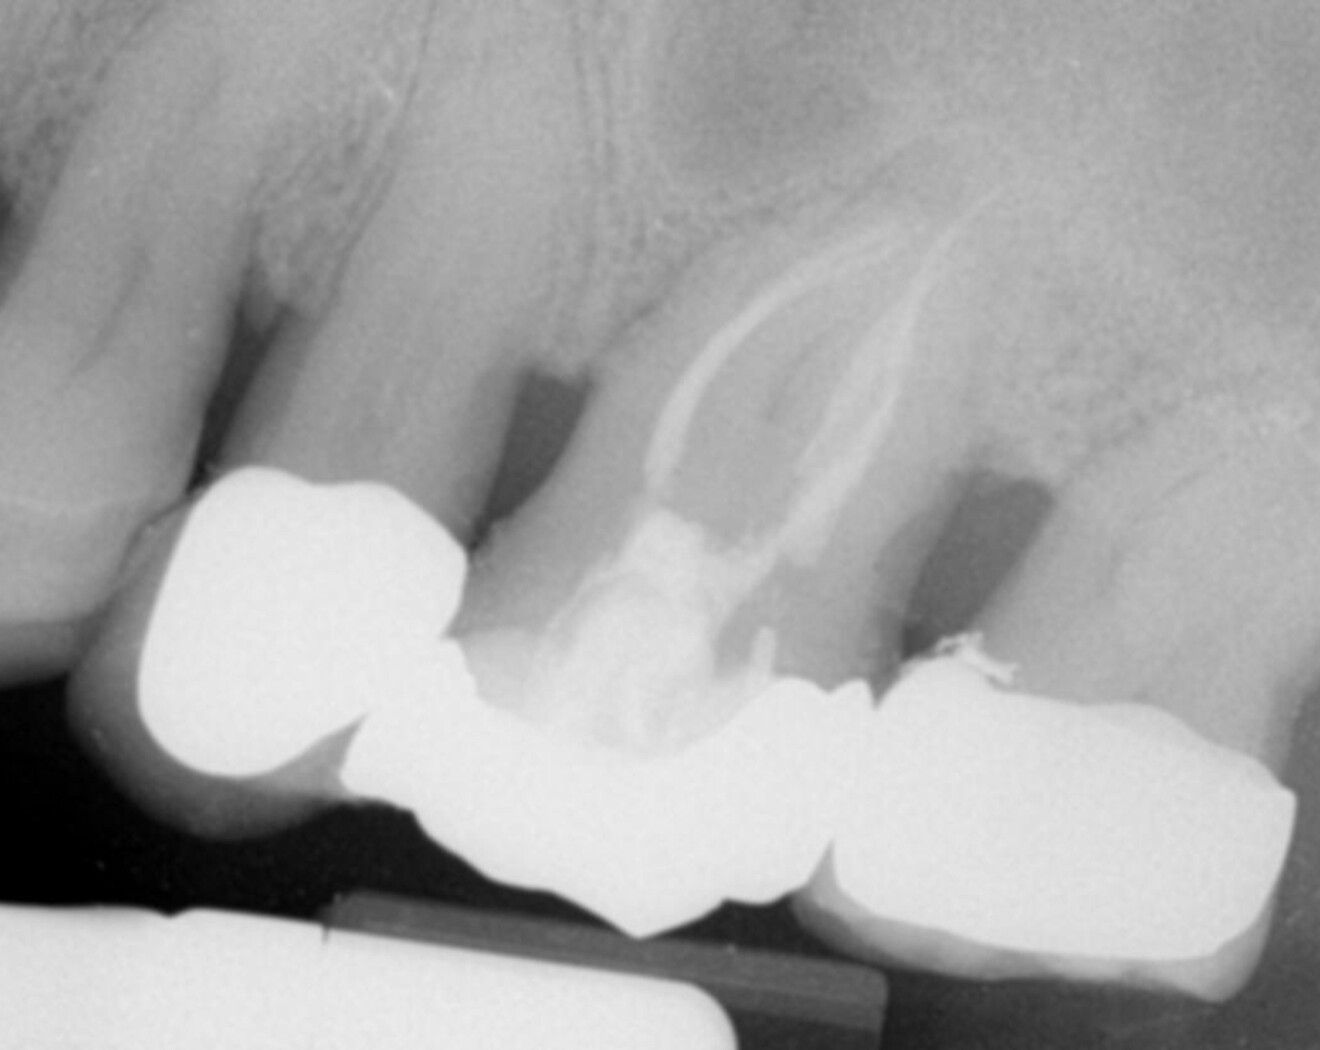

The mandibular molar too was necrotic and presented with internal calcification. This is the result of the chronic activation of inflammatory pathways in the body, which can lead to the formation of micro blood vessels within the pulp that later calcify as a defensive response to slow, chronic aggression. This kind of calcification can cause irreversible pulpitis and later necrosis of the pulp. In this case, the calcification could clearly be seen all along the root canal system, reaching almost to the apical area (Fig. 9).

Fig. 9: Pre-op radiograph showing calcification along the entire length of the canals.

I chose to use the Traverse and ZenFlex file systems with full rotation motion for its high cutting efficiency to remove the calcifications, starting with the 25/0.08 Traverse file (Fig. 10). All files were used with a pecking motion. The postoperative radiograph showed good healing (Fig. 11).

Fig. 11: Post-op radiograph after removing the calcification and achieving 3D vertical obturation.